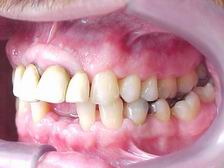

Vista Lateral Direita (ANTES)

Vista Lateral Esquerda (ANTES)